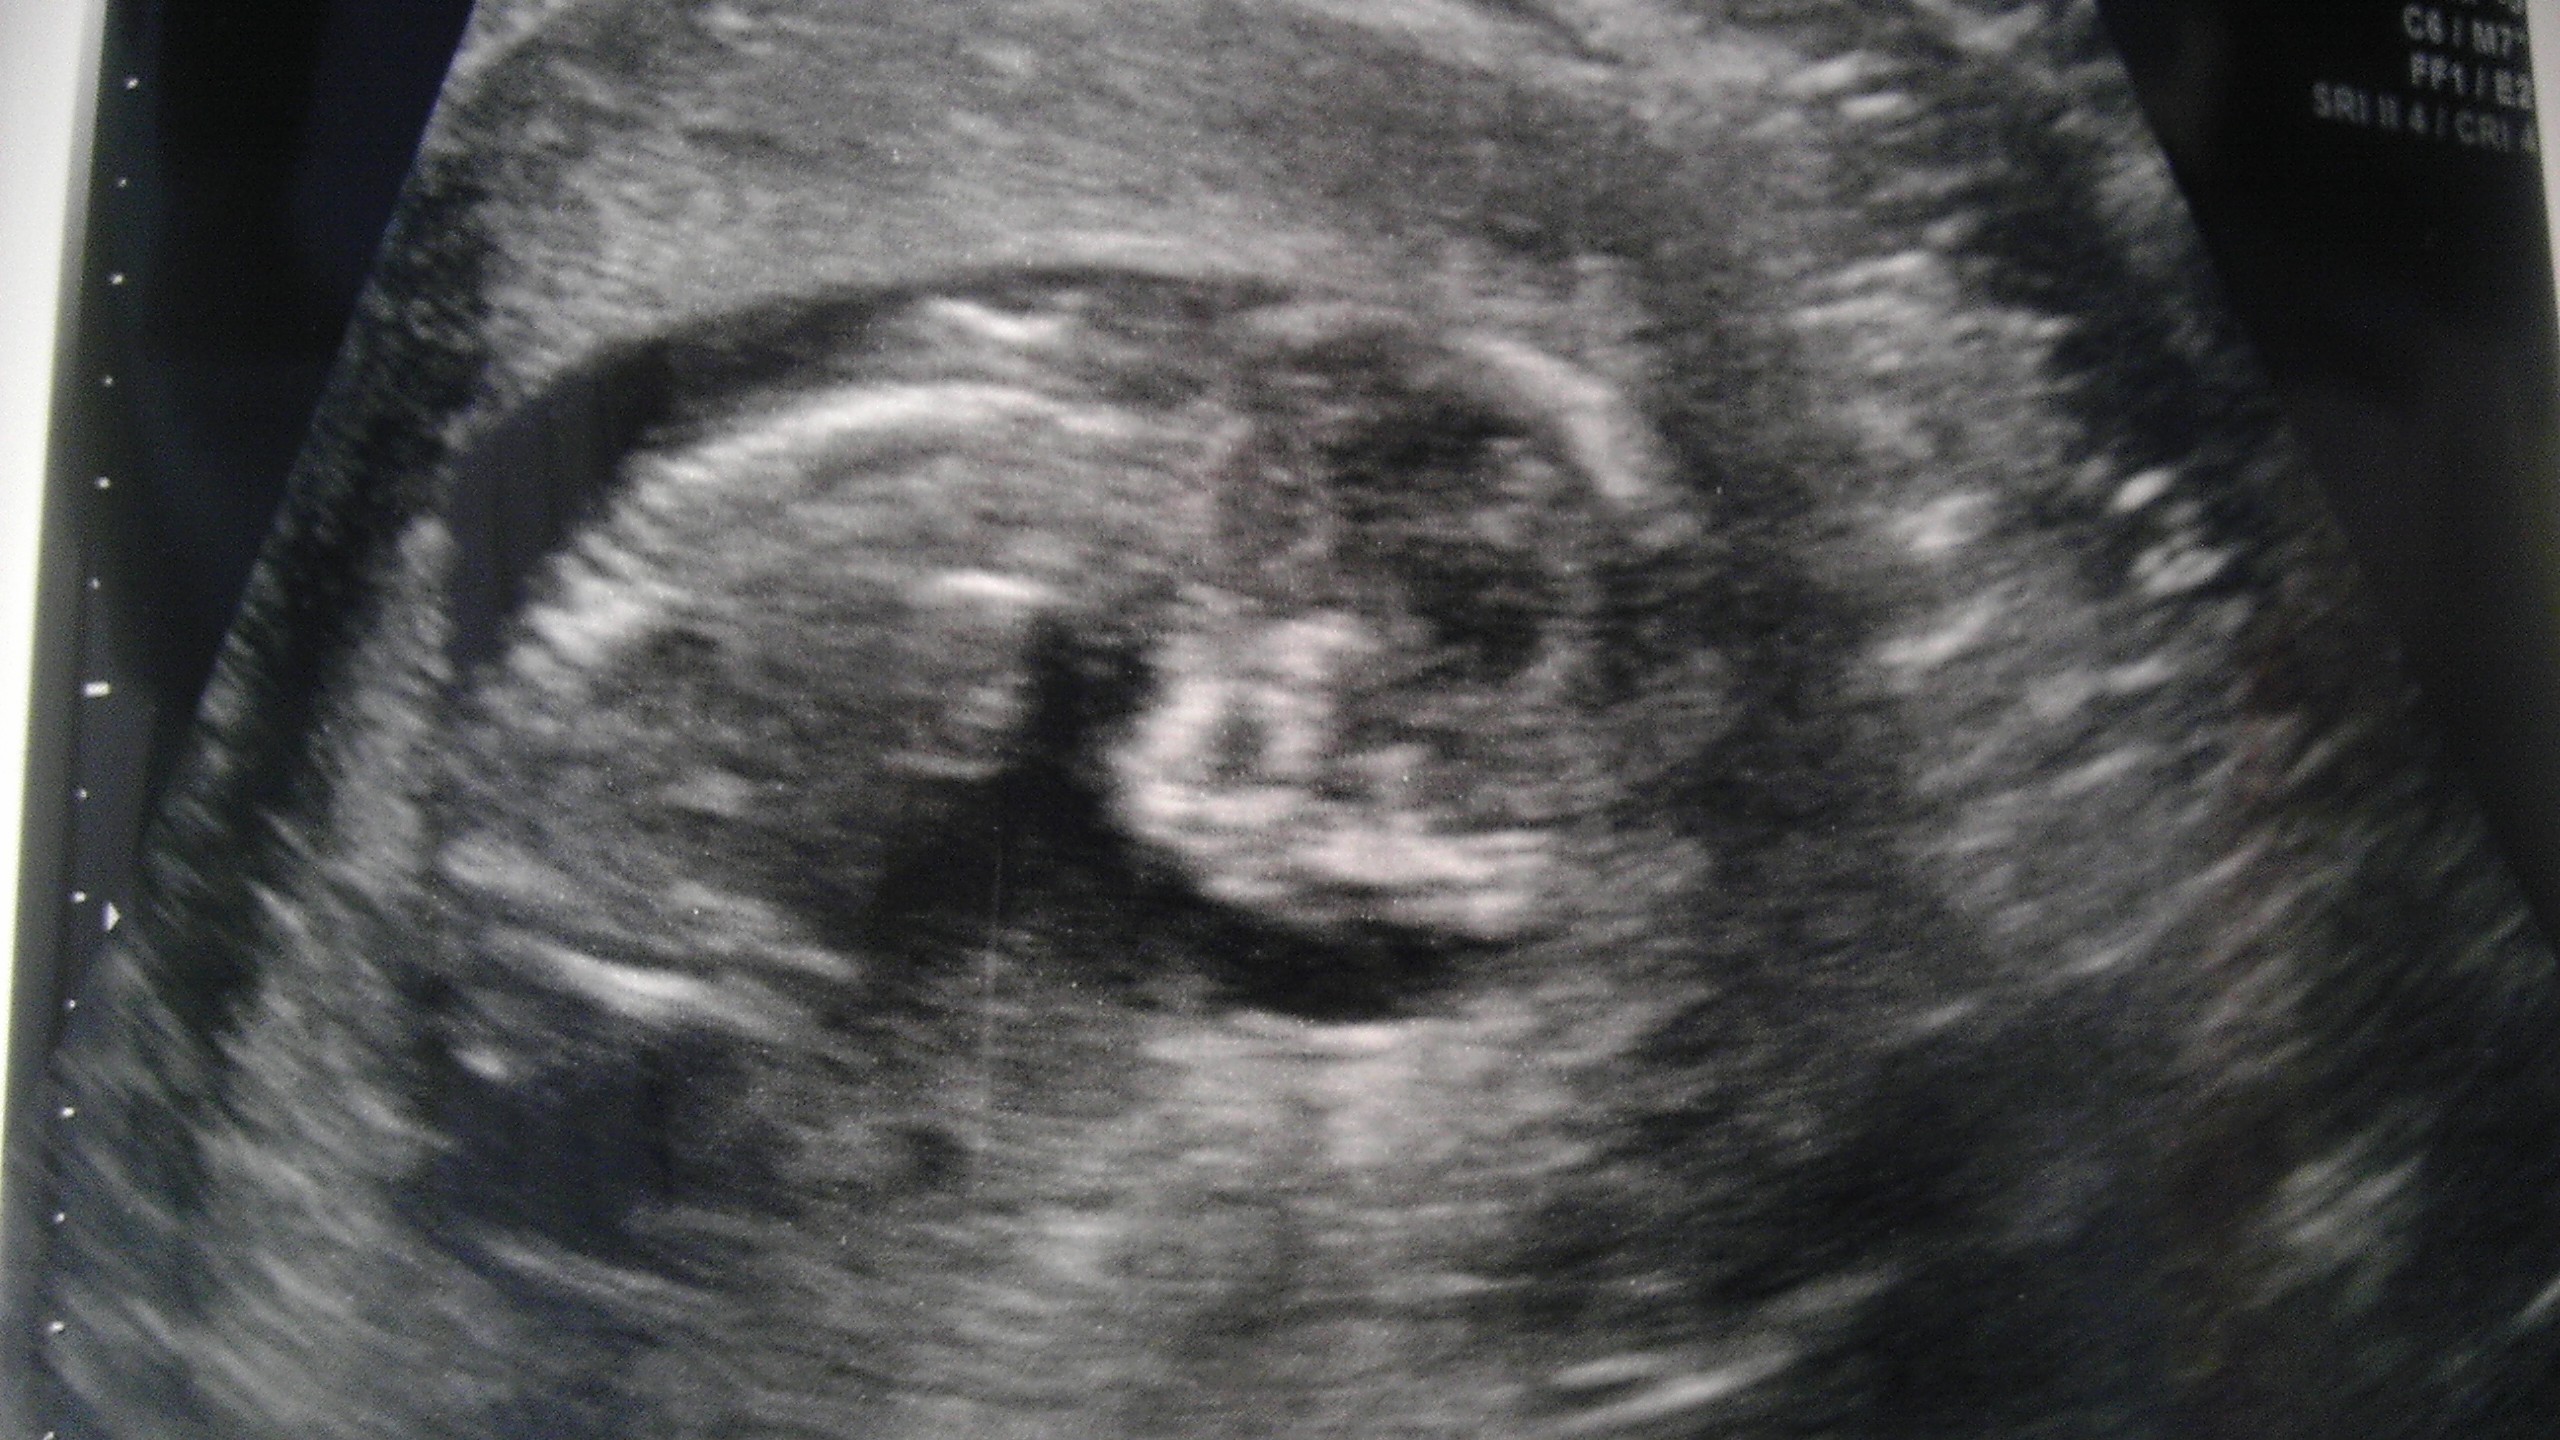

Had my big anatomy scan today at 22 weeks and it is definitely a little girl!!